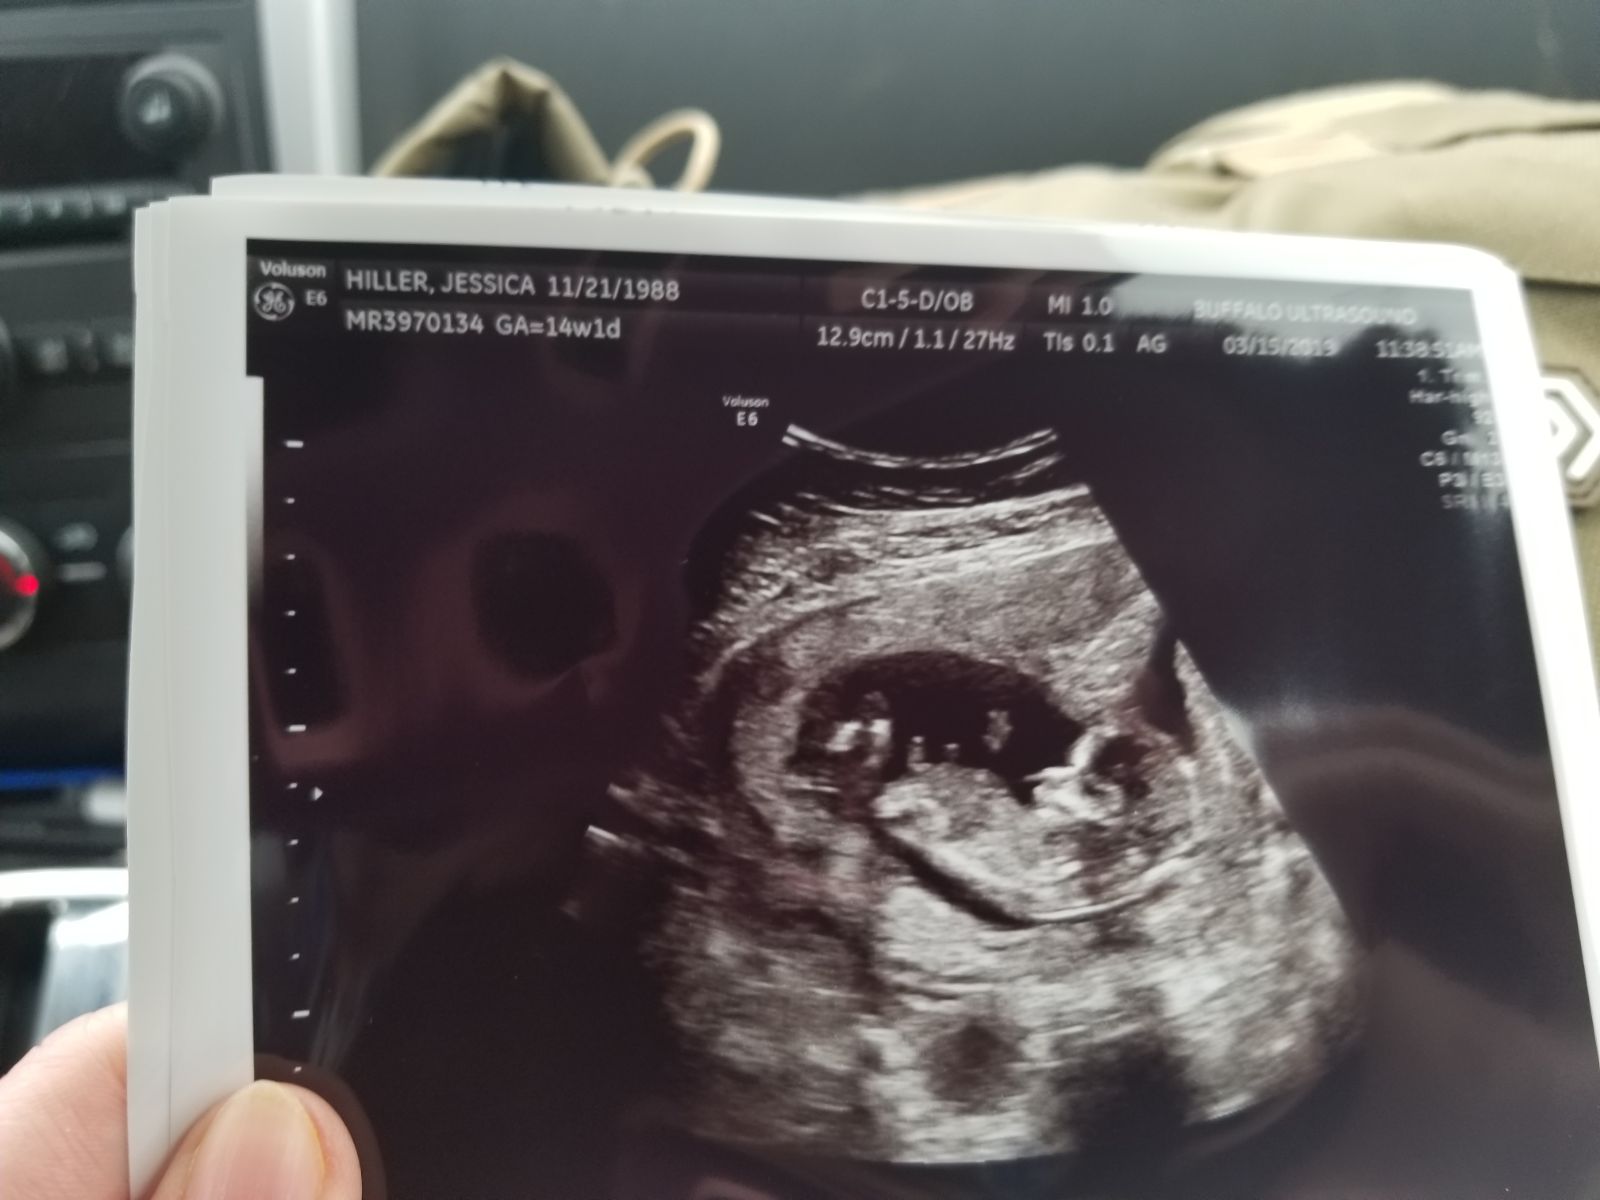

newest member of family little isale